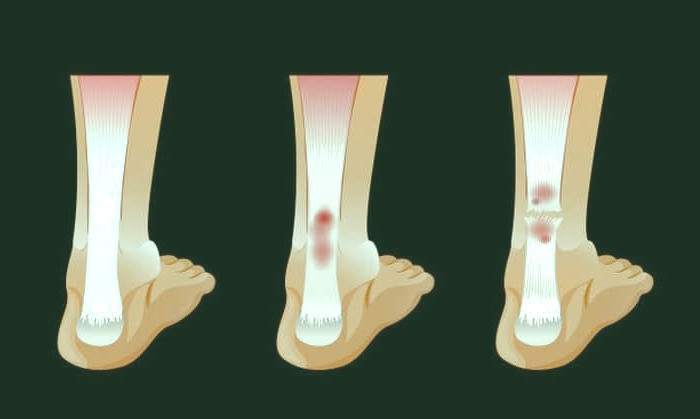

شکستگی باز (مرکب) :

استخوان شکسته از طریق پوست خارج می شود و احتمال عفونت و خونریزی خارجی بیشتر است .

شکستگی بسته (ساده) :

استخوان شکسته اما پوست را سوراخ نکرده است .

شکستگی بسته

شکستگی مویی :

شایع ترین شکل شکستگی است و قسمت های شکسته شده جابه جا نشده اند و نیرویی که موجب این شکستگی شده قوی نیست.

شکستگی مویی